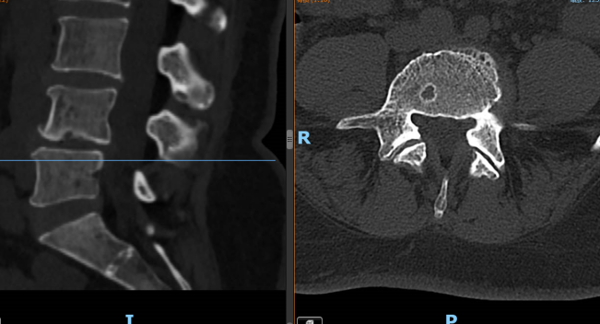

▲③术前CT片

“医生,我这半年来腰痛的厉害,右腿现在又痛又麻,走路都困难,有什么办法处理吗?”在骨科诊室,患者谭阿姨(化名)苦恼地说道。老虎机app 骨科脊柱外科专业专家欧裕福副主任医师详细询问谭阿姨病史,并为她安排了细致的检查,最终诊断为腰椎管狭窄症+腰椎滑脱症。

结合谭阿姨下腰部明显压痛、右下肢疼痛及活动障碍等症状,骨科脊柱外科团队经过多次术前讨论,并联合麻醉手术中心团队,为谭阿姨制定了个性化的诊疗方案,决定运用经皮内镜下腰椎减压融合技术为患者进行治疗。